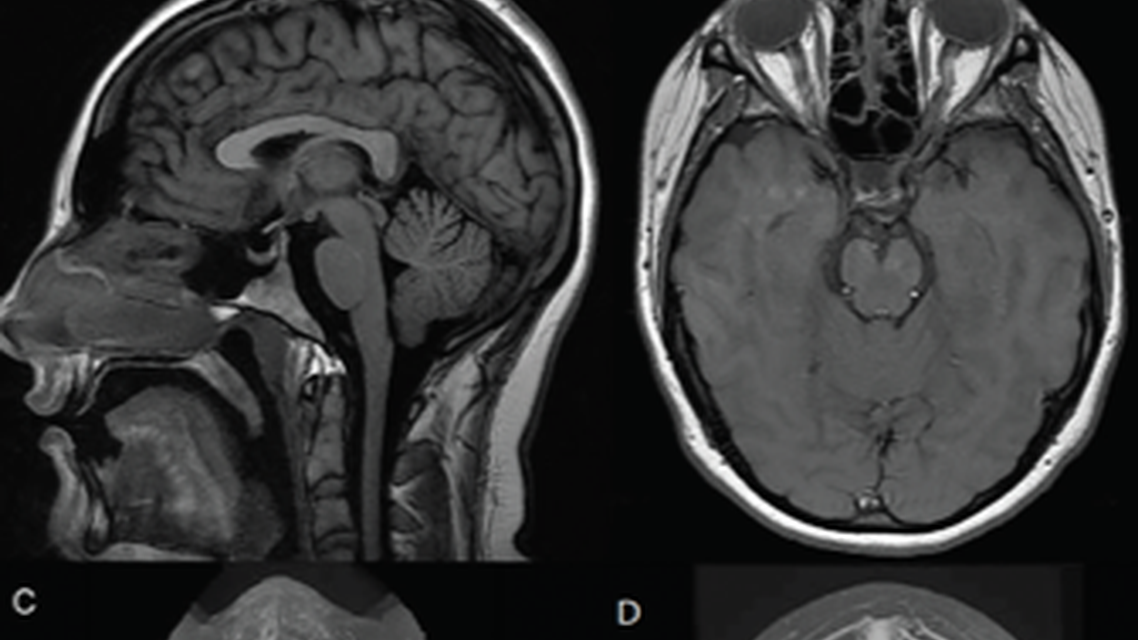

In 2018, the European Headache Federation published guidelines on the diagnosis and treatment of IIH.1 The diagnosis of IIH is made using the Friedman criteria, whereas the International Classification of Headache Disorders (ICHD-3) outlines the diagnostic criteria of the associated headache (Table). There are diagnostic criteria for IIH and IIH without papilledema (IIHWOP). Individuals with IIH often present for the evaluation of headache but may also present because of vision complaints. Evaluation should follow a structured approach (Figure 1). If papilledema is present, the next diagnostic step is to obtain an MRI with and without contrast and venography to exclude the presence of a structural abnormality or cerebral venous sinus thrombosis (CVST). There may be neuroimaging signs suggestive of increased ICP (Figure 2). If a secondary cause of papilledema is not identified, a lumbar puncture must be performed. Opening pressure of 25 cm or more cerebrospinal fluid (CSF) and otherwise normal CSF confirms the diagnosis of IIH. There is a “gray zone” from 25 to 30 cm CSF that may be a normal opening pressure for some but pathologic for others, making the clinical history and other diagnostic criteria exceedingly important.2 Individuals with IIH should have normal neurologic exams with the exception of 2 common cranial nerve abnormalities (cranial nerve 6 palsy and dysfunction of cranial nerve 2—papilledema and visual field defects).1,3 Ocular coherence tomography (OCT) is an objective way to quantify papilledema based on retinal nerve fiber layer thickness. Similar to the funduscopic exam, this can be monitored serially.2 In IIHWOP, the diagnosis can be made if all the above criteria are met except papilledema and cranial nerve 6 palsy is present. If cranial nerve 6 palsy is not present, there should be at least 3 features on neuroimaging consistent with elevated ICP to make a diagnosis of probable IIHWOP.1